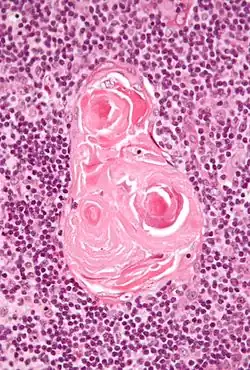

Вилочковая железа имеет дольчатое строение, в ткани дольки различают корковое и мозговое вещество. Корковое вещество расположено на периферии дольки и в гистологическом микропрепарате выглядит тёмным (в нём много лимфоцитов — клеток с крупными ядрами). В корковом веществе расположены артериолы и кровеносные капилляры, имеющие гемато-тимусный барьер, препятствующий заносу антигенов из крови.

Клеточный состав мозгового вещества представлен опорными эпителиальными клетками, звездчатыми клетками, макрофагами. Имеются также выносящие лимфатические сосуды и тельца Гассаля.